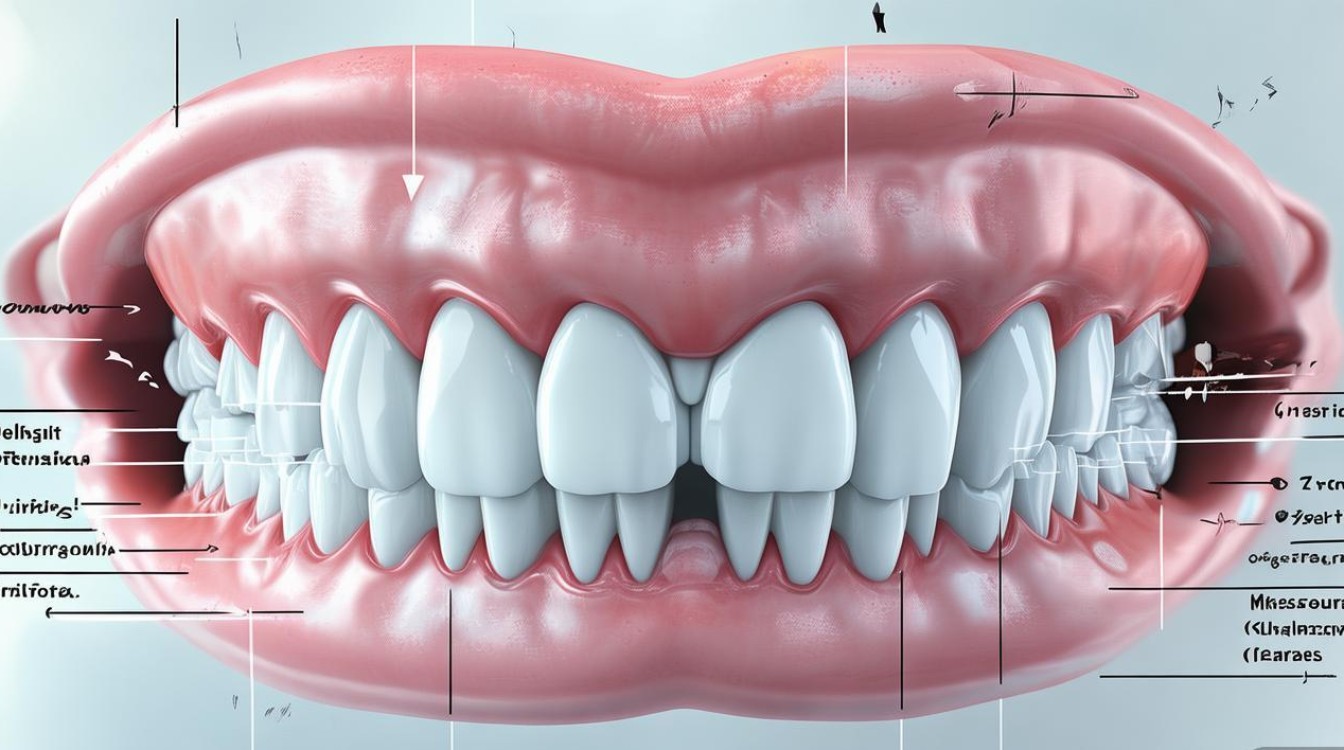

牙齿问题的复杂程度:

- 简单情况: 如轻微的牙齿拥挤、小范围的牙缝、简单的扭转等,可能只需要6-12个月。

- 中等复杂情况: 如中度拥挤、需要少量拔牙、涉及咬合关系调整(如深覆合、深覆盖)、需要移动牙齿较多等,通常需要12-20个月。

- 复杂情况: 如严重拥挤、需要大量拔牙、需要显著改变颌骨关系(需要配合正颌手术)、涉及复杂的咬合重建、需要大量移动牙齿(如压低、伸长、旋转等)、有牙周病需要先治疗等,可能需要20个月甚至2年以上。